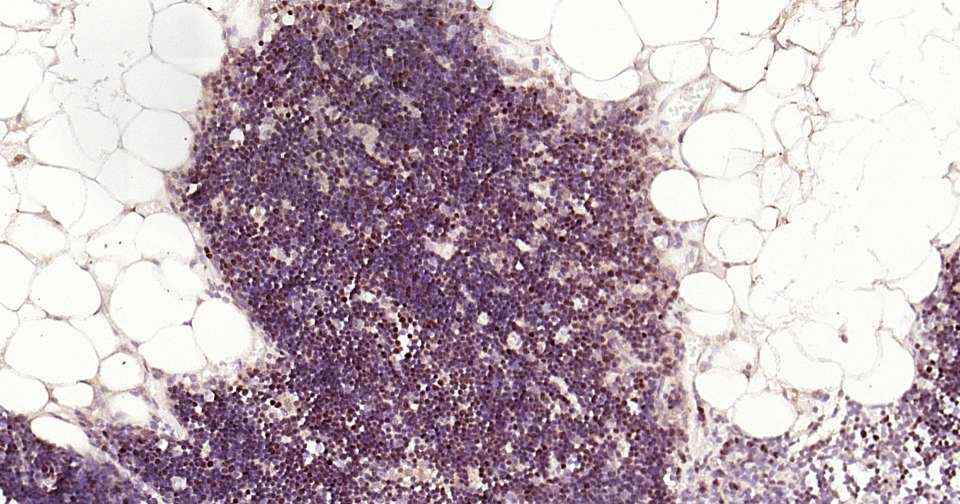

Immunohistochemical analysis of paraffin embedded human thymus tissue slide using IHC0328H (Human LEF1 Kit).